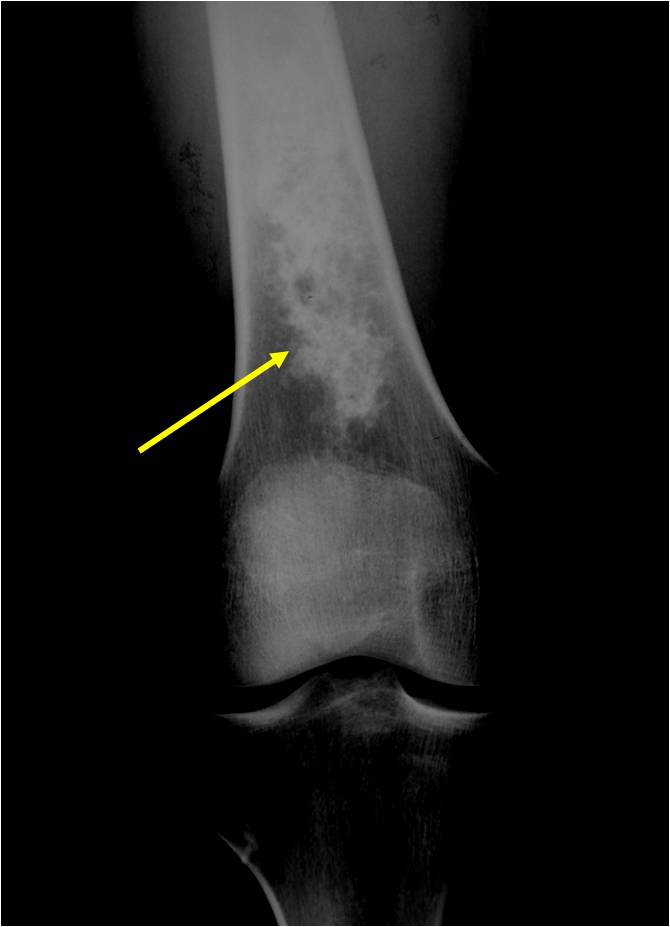

- Localized, radiolucent defect usually with punctate calcifications

- Calcifications are typical but not always present

- Matrix may demonstrate various degrees of calcification

- Calcifications are stippled, punctate, popcorn like calcifications and “Ring and Arc” calcifications

- Cartilage tumors grow in a lobular manner. The perimeters of the lobules undergo

- enchondral ossification that may calcify. If the entire perimeter of the lobule calcifies it appears

- radiographically as a “Ring”. If a portion of the perimeter of a lobule calcifies it forms an “Arc” on

- an X-ray.

- May be located centrally or eccentrically

- Grows eccentrically or concentrically (phalanges)

- Cortex may be scalloped and thinned in the phalanges

- Most commonly found in metaphysis

Metaphyseal Tumor Heavy Calcifications Ring and Arc Pattern of Calcifications Minimal Endosteal Scalloping No Cortical Destruction No Periosteal Reaction No Cortical Destruction No Soft Tissue Component

Geographic Lesion Bony Expansion Minimal Calcification Some Enchondromas do not calcify